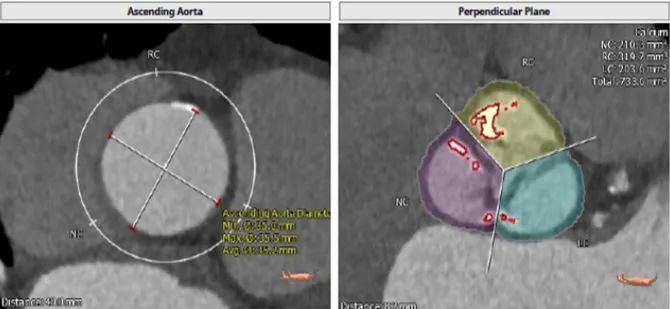

根部解刨

患者为三叶瓣,重度钙化,瓣环29.1 mm,LVOT28.6 mm,预计瓣口开口29.1 mm,STJ 32.3 mm,窦部空间大,左右冠高度分别为16.2 mm和19.8 mm,预计24mm球囊预扩。